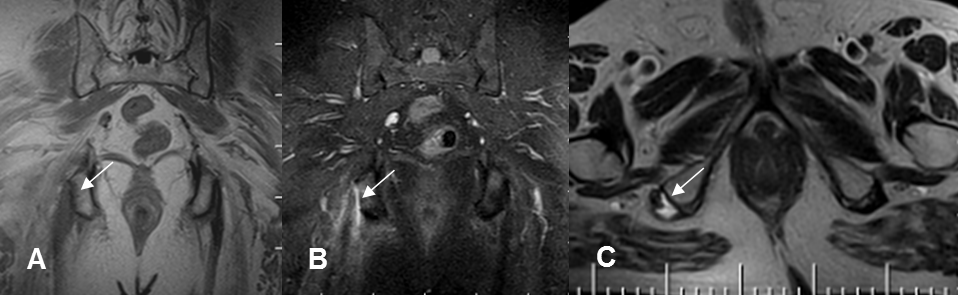

Fig 141 A. Ruptura muscular.

A: RM coronal en T1, B: RM coronal en STIR y C: RM axial en T2. Solución de continuidad en la mayoría de fibras, sobre el origen de los isquiotibiales del lado derecho, por ruptura no retraida.